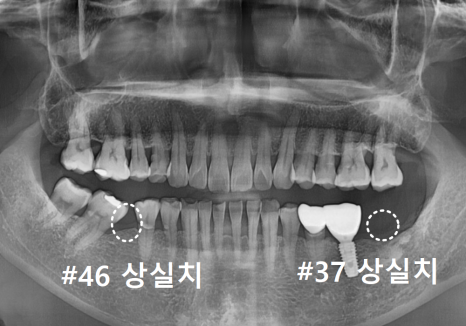

오른쪽 아래(#46)와 왼쪽 아래 맨 끝(#37)

치아를 발치한 지 꽤 오래된 상태였죠.

| 1) 오른쪽 어금니#47,48 어금니들이 빈 곳으로 많이 쏠려 #46 상실 부위에 임플란트를 심을 공간이 부족한 상태2) 왼쪽 어금니위쪽 어금니(#27)가 맞물릴 곳이 없어 아래로 정출되어 내려온 상태 |